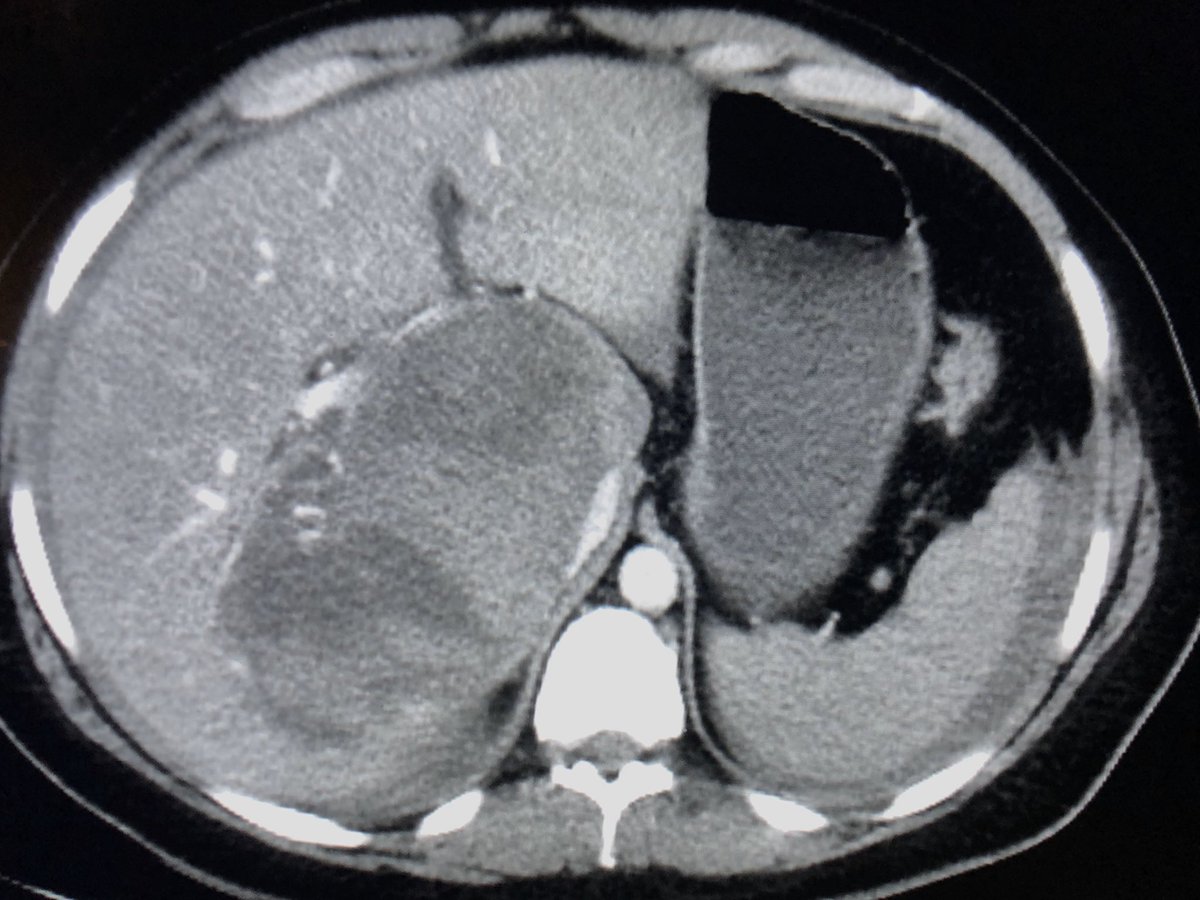

Bleeding hepatic adenoma. The things that just walk into your emergency department....pic.twitter.com/rnU8L54oSk

Hvala. Twitter će to iskoristiti za poboljšanje vaše vremenske crte. PoništiPoništi -